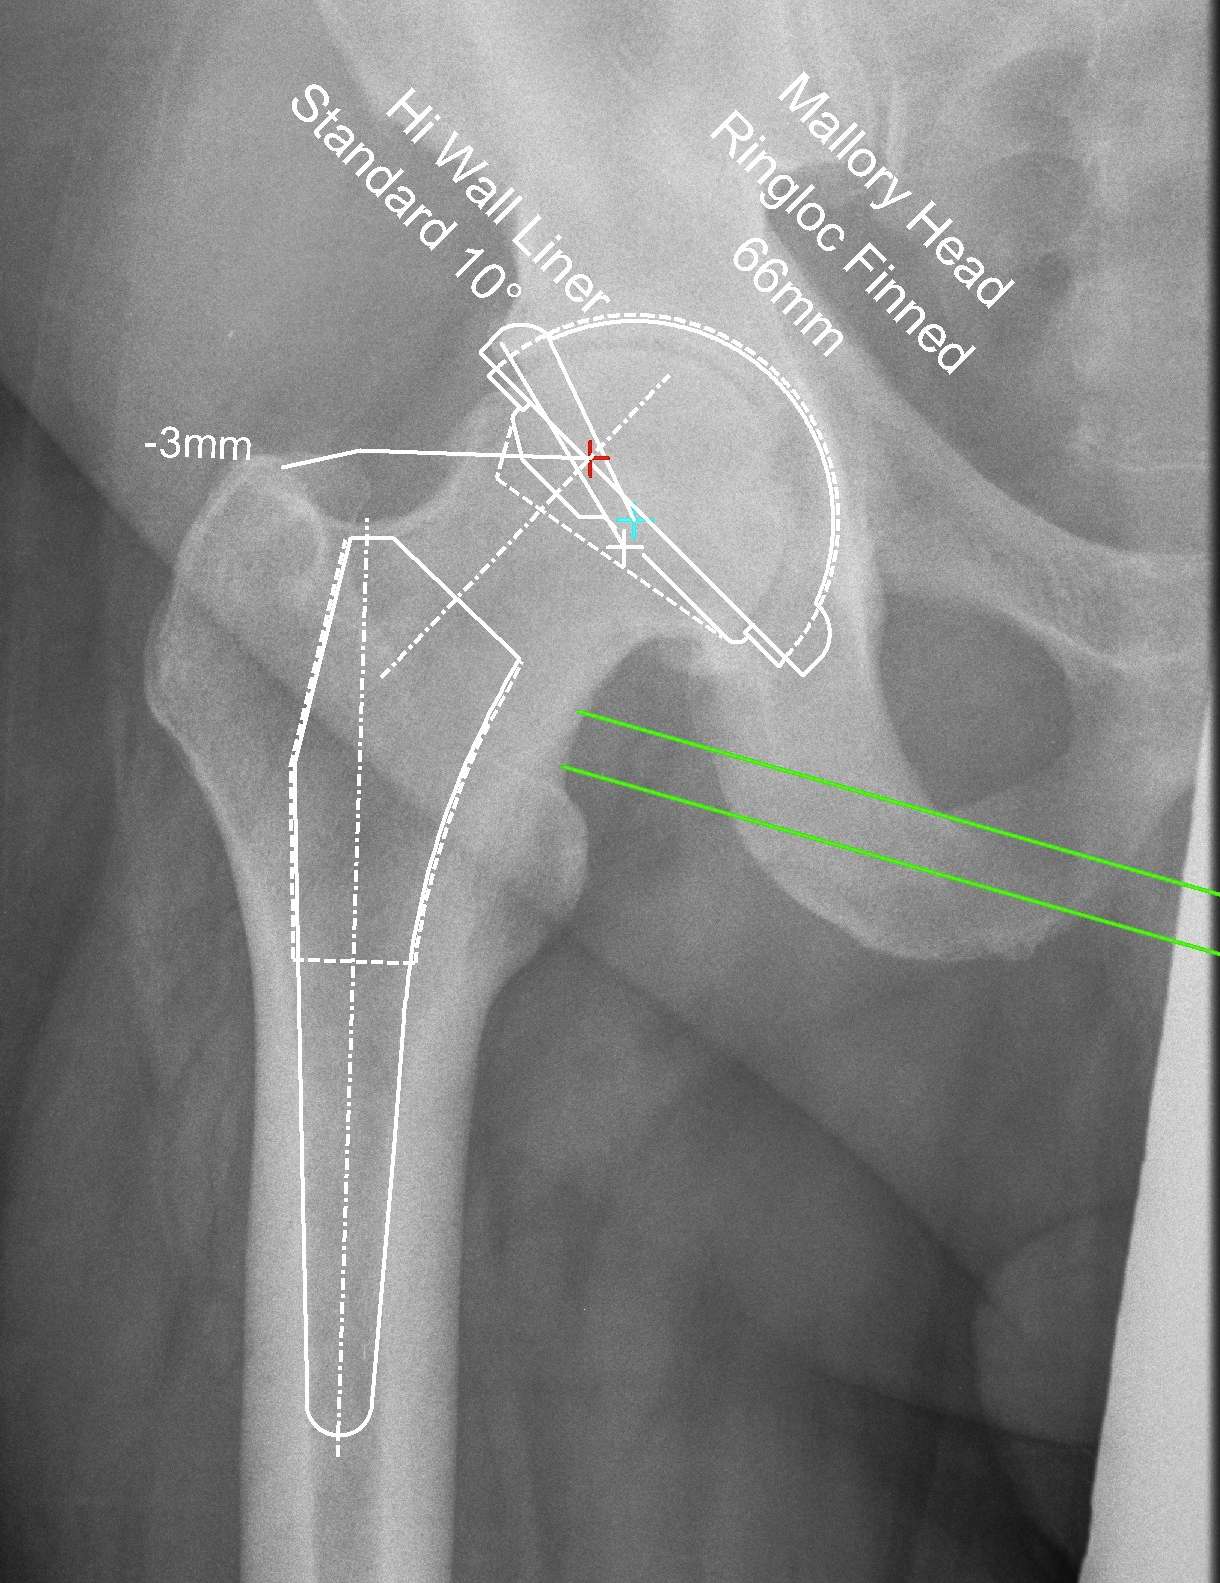

Reproduce the normal anatomical centre of rotation

Restore femoral offset

Maintain equal leg lengths

Usually template off normal hip

1. LLD

2. Offset

3. Femoral component

4. Acetabular component

5. Osteotomy / femoral seating